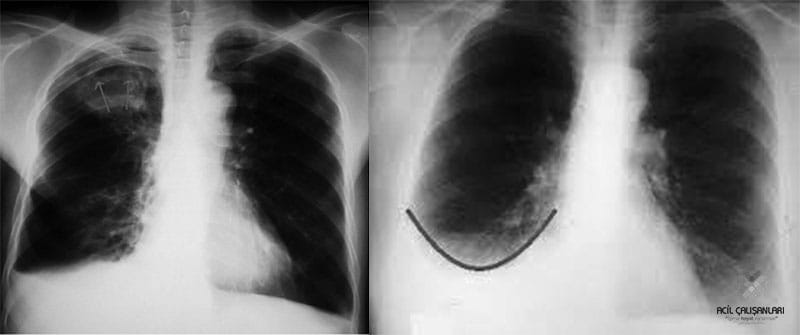

Derin İnspiryum: Posteroranterior akciğer grafisi tam inspirasyonda (hastaya derin nefes aldırılarak) elde edilmelidir. Uygun inspirasyonda elde edilen bir grafide diyafram 8.-10. posterior ya da 5.-6. anterior kotlar seviyesinde olmalıdır. Yetersiz inspirasyon ya da ekspirasyon sırasında elde edilen grafiler parankim değerlendirmesinde hatalara yol açabilir, incelemenin tekrarı gerekebilir.

Bazı durumlarda inspiryum grafisine ilave olarak ekspiryum sonu grafi de çekilebilir.

• Hava hapsi

• Pnömotoraks (az miktarda olan pnömotoraksı göstermek için)